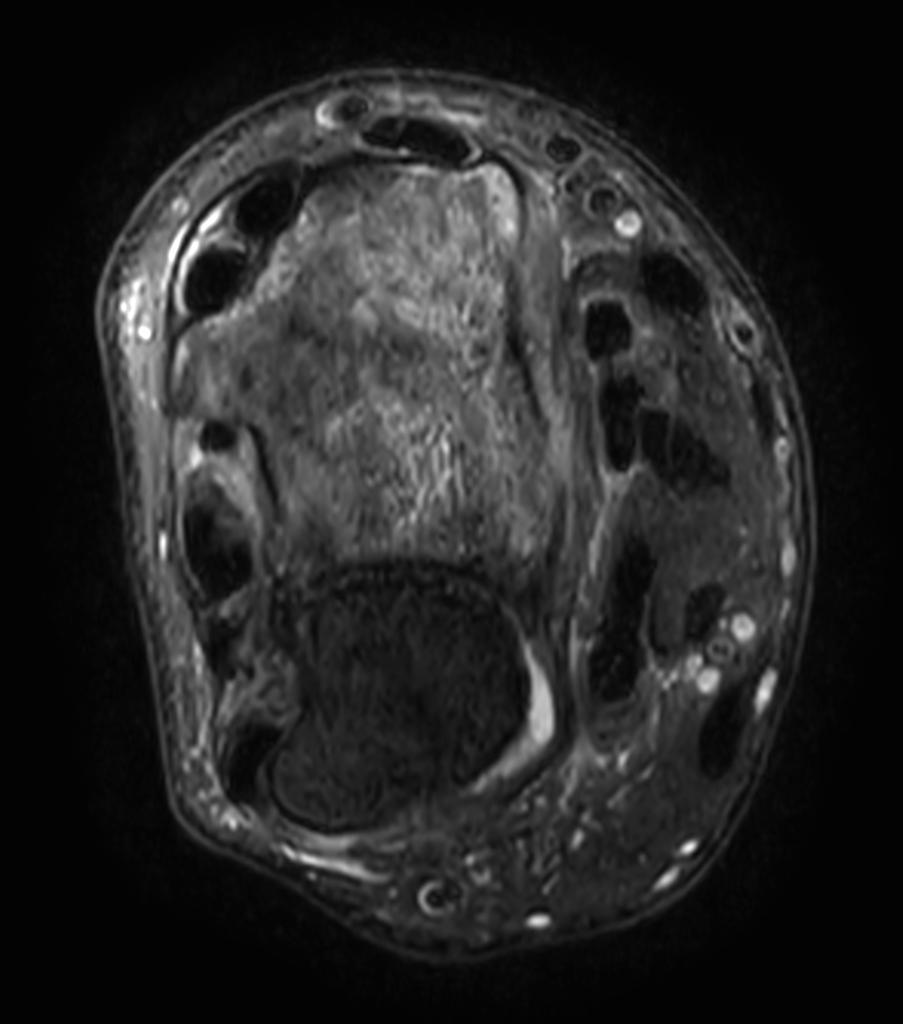

Patient with a wrist fracture. Compressed SENSE is used in all sequences, reducing the scan time while maintain equal image quality compared to scans without Compressed SENSE. 3D sequences have been added to this ExamCard with a comparable in-plane resolution but much thinner slices. Due to the shorter scan times that can be achieved thanks to Compressed SENSE, these 3D sequences could potentially replace the 2D sequences providing more confidence in making the diagnosis.

2D Axial PDw SPAIR

3D Axial PDw SPAIR